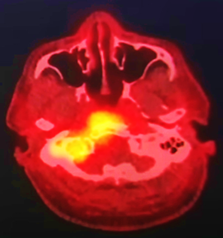

<출처 : Otolaryngology Case Reports 2022>

호주 67세 남성의 뇌 CT

주변보다 노랗게 보이는 곳이 뇌 뼈에 염증이 생긴 것.

면봉 솜의 잔여물이 귀 안쪽의 염증을 일으켜 귀 뼈를 타고 뇌 뼈까지 퍼진 것이다.